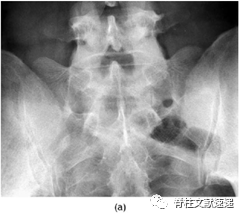

1、X线:腰骶移行椎的典型鉴定方法就是通过侧位和弗格森位X线片(即X线球管向头侧倾斜30°,可更好的显示腰5横突及其与骶骨的关系)来鉴定。

图2注:(a)Ib型LSTV,L5双侧横突增宽,但与骶骨未形成关节;(b)IIa型LSTV,L5单侧横突增宽,单侧假关节形成;(c)IIb型LSTV,L5双侧横突增宽,双侧假关节形成;(d)IIIa型LSTV,L5单侧横突增宽,并与骶骨形成骨性融合;(e)IIIb型LSTV,L5双侧横突增宽,并与骶骨形成骨性融合;(f)IV型LSTV,左侧形成骨性融合,右侧形成假关节。